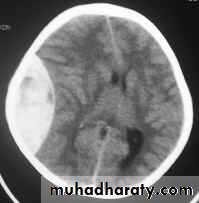

5. Hydrocephalus

a. Acutely due to obstruction of CSF outflow due to intraventricular blood.

b. Delayed post-traumatic communicating hydrocephalus due to impaired CSF reabsorption following traumatic subarachnoid haemorrhage

Intraventricular blood can lead to Hydrocephalus